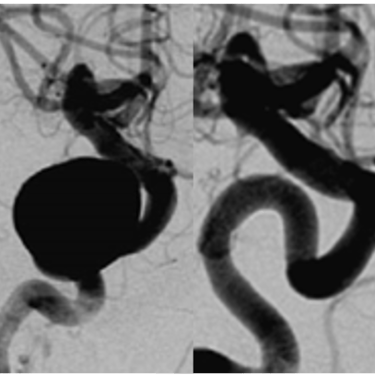

Gehirnaneurysma (Clip, Coil, Flow Diverter)

Als klinisch-wissenschaftlicher Neurochirurg habe ich großes Interesse daran, meine klinischen Aufgaben durch Wissenschaft und Forschung in den von uns behandelten neurochirurgischen Erkrankungen zu ergänzen. Seit meinem Studium und postgraduellen Ausbildung war ich an Grundlagenforschung, klinischer und translationaler Forschung beteiligt und habe bisher mehr als 450 wissenschaftliche Veröffentlichungen zur medizinischen Fachliteratur beigetragen sowie erfolgreich kompetitive Drittmittel eingeworben. Wir haben die Behandlung traumatischer zerebrovaskulärer Erkrankungen, genetische Polymorphismen im Zusammenhang mit zerebralen Aneurysmen und aneurysmatischen Subarachnoidalblutungen sowie die Behandlung von Thrombozytenaggregationshemmern im Zusammenhang mit der Flow-Diverter-Behandlung von zerebralen Aneurysmen untersucht, um nur einige Projekte zu nennen.